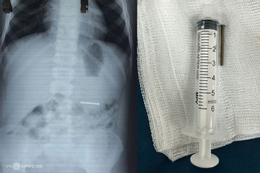

Trong quá trình nội soi mũi, các bác sĩ phát hiện nhiều dị vật màu trắng tròn làm tắc nghẽn hai hốc mũi bé trai 3 tuổi. Ban đầu ước tính có 7 dị vật ở hai ống mũi. Tuy nhiên, do trẻ không hợp tác, các bác sĩ quyết định gây mê để can thiệp.

Kết quả sau thủ thuật cho thấy có tới 12 hạt xốp được lấy ra. Một số dị vật nằm sâu trong khe mũi và bị tình trạng viêm che lấp, gây khó khăn trong chẩn đoán hình ảnh ban đầu.